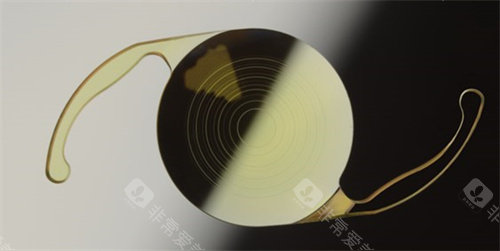

家人们,我做白内障三焦晶体植入手术已经有一段时间啦,现在来给大家好好分享下我1个月和6个月的真实感受,真的就像告别了“毛玻璃”国内外,重见清晰光明!

三焦切换超流畅,就跟变魔术似的,想看哪儿,眼睛立马就能适应。

而且啊,这眼睛就跟上了润滑油的机器一样,不管是看远、看中还是看近,都能快速调整到理想状态,一点儿都不费劲。

我都忍不住感叹,这三焦晶体植入手术简直就是我的救星,让我重新找回了清晰的视野。